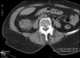

Invasive colon cancer

Colorectal cancer (CRC), also known as bowel cancer, colon cancer, or rectal cancer, is the development of cancer from the colon or rectum (parts of the large intestine). Signs and symptoms may include blood in the stool, a change in bowel movements, weight loss, and fatigue.Most colorectal cancers are due to old age and lifestyle factors, with only a small number of cases due to underlying genetic disorders. [Source: Wikipedia ]